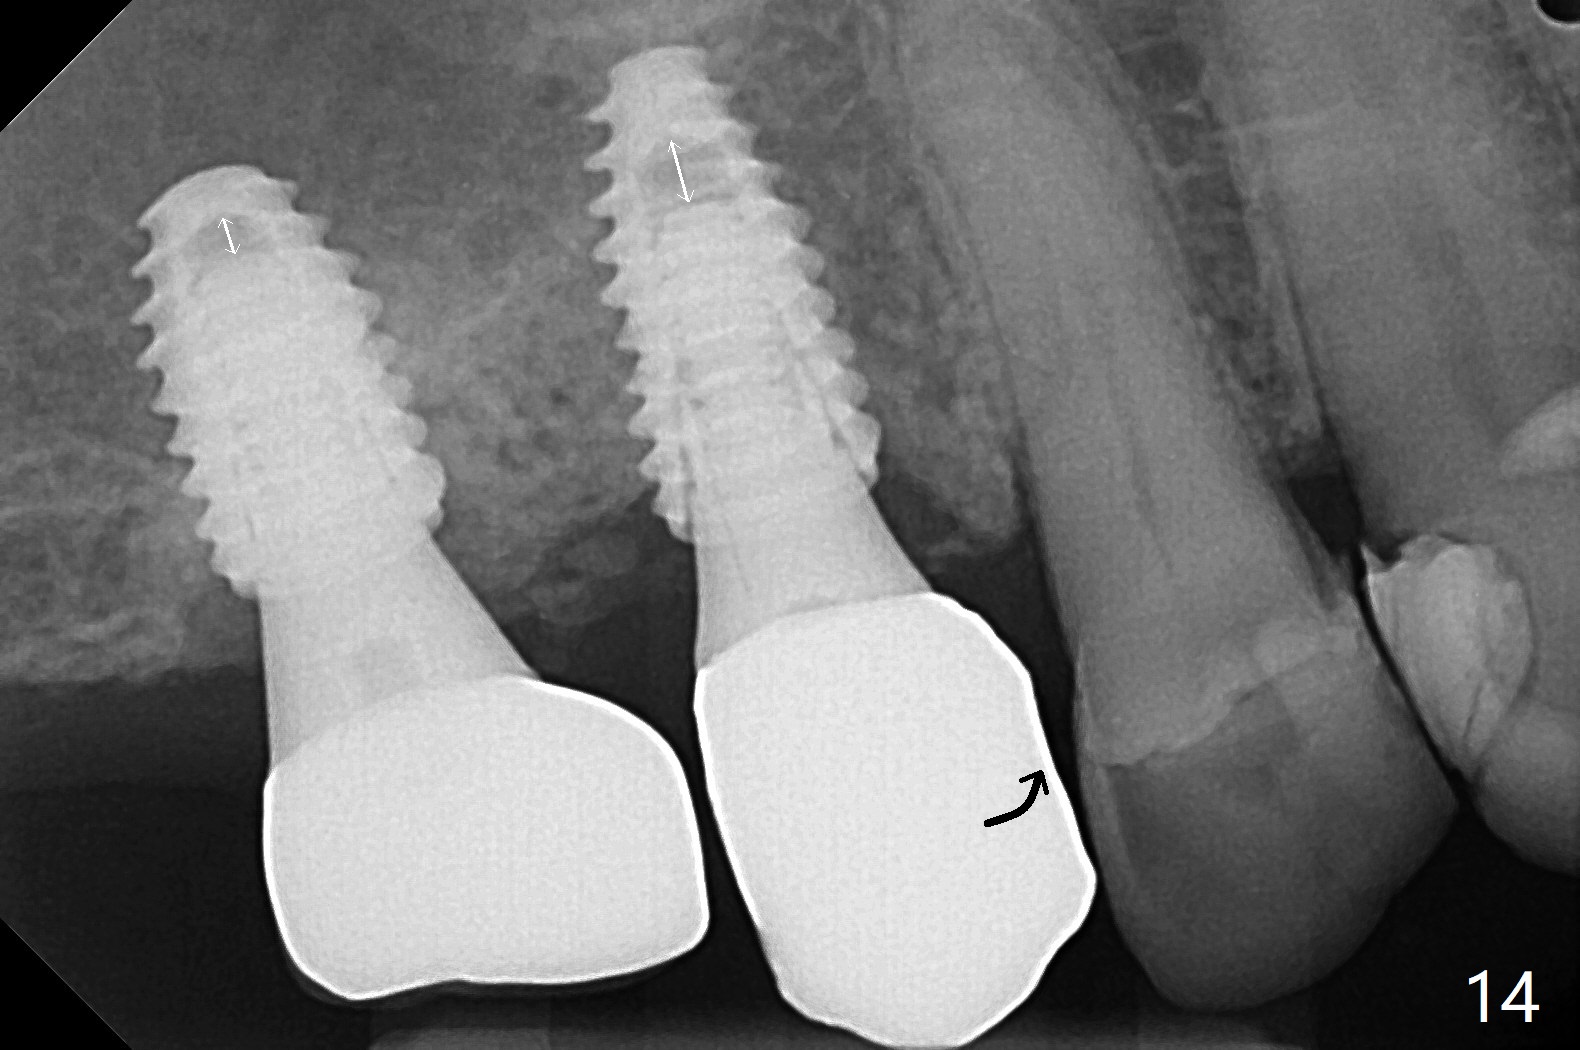

Osteotomy at #3 is performed last (Fig.1,2); as planned, a 4 mm cortical tap is used with guide for sinus lift. Unfortunately the sinus membrane is perforated. Implant placement is aborted. Instead Osteogen plug is inserted into the osteotomy, which is fixed in place by acrylic extending from the provisional at #4. Osteotomy for #3 implant will be attempted with control of the depth in 4 months. The patient has allergy to Amoxicillin (rash). When switching to Clindamycin, she develops diarrhea and loses 10 pounds. There is no abnormality at the site of #3 or 4 nearly 3 months postop (Fig.3). The next surgery will be most likely conducted without antibiotic 4 months postop. Try to draw blood for PRF. Take PA for #12 and 13 for possible impression. Remove the 3 temporary crowns, seat the guide across the arch and use no-stop fixture mounts at #4, and possibly 12 and 13. Follow the original drill sequence (check perforation after each drill, Fig.11) and use DIONavi sinus approach kit. Also load an appropriate stop for the round bur for sinus lift before hand. Mixture allograft with Metronidazole and PRF. In fact everything goes on as smoothly as planned. Osteotomy at #3 is underprep (3.5 mm in diameter drill instead of 4.0). The sinus floor appears to remain to be absent; 3.2 mm round bur is used for lift, alternating with water pumping. Following insertion of 3 pieces of PRF membranes and Vanilla Graft (Fig.4 *), a 4x10 mm dummy implant is placed. After additional bone graft (Fig.5 *), a final 4.5x7.3 mm implant is placed ~10 Ncm. The implant is placed deeper ~ 1 mm, followed by a 5.5x3 mm healing abutment (Fig.6). The implants at #12 and 13 seem to have osteointegrated (Fig.7). Impression is taken for #4, 12 and 13 with limited vertical space (Fig.8,9). An implant at #14 is being considered. There is faint bone graft around the apex of the implant 4 months postop (Fig.10). The implant sustains 25-30 Ncm torque when a 5.2x4(3) mm cemented abutment is placed. A permanent crown is cemented nearly 5 months postop (Fig.11). For the best cosmetic and masticating results, the occlusal surface should have certain degree of morphology, such as the buccal cusps (Fig.12 white curved lines). The abutment at #3 is placed and torqued to 30 Ncm before re-cementation of the repaired crown (increased occlusal surface contact). In fact the abutment at #4 is incompletely seated with a gap (Fig.13 <). The composite at #5 is dislodged while #3 crown is being repaired (*). The abutment at #4 is loose >1 year post cementation. The abutment remains incompletely seated (gap and longer apical space (double arrows)) when the abutment/crown complex rotates lingual mesiobuccal (Fig.14 curved arrow). Further proximal reduction and lingual rotation distobuccal leads to complete seating (Fig.15). It appears that incomplete seating at #13 is associated with hex mismatch (Fig.16, large apical space), which will be fixed next visit. One week later, the crown and abutment of #4 are seated together after crown repair (Fig.17). Since the abutment margin is subgingival, the crown is cemented, removed with abutment for residual cement removal and reseated with the abutment with torque at 30 Ncm. After this, the crown and abutment of #13 is reseated after mesiobuccal surface is trimmed (Fig.18), followed by pick up impression. A few days later, the crown/abutment are inserted together smoothly, the former cemented and the complex unscrewed for residual cement removal and last torqued at 30 Ncm without any X-ray confirmation.